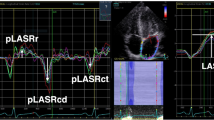

Strain echocardiography

Strain measurements were performed off-line in the four-chamber, long axis- and two-chamber views. All off-line analyses were performed by an investigator experienced in speckle tracking analysis using the EchoPAC workstation version 201(GE Medical Systems, Milwaukee, Wisconsin, USA). From the strain analysis, we calculated the longitudinal strain of the free RV wall and the global longitudinal strain (GLS) for the LV. Myocardial strain (S) is presented as fractional change (%) in length between two time points, end-diastole (L0) and end-systole (L) and calculated as: (L – L0)/L0 × 100. Negative values of strain indicate myocardial shortening. Impaired LV GLS and RV free wall strain was defined as > − 16% [18] and > − 24% [19] respectively.

Echocardiographic variables (Table 3, Figs. 1, 2, 3 and 4)

Left ventricle

After induction of anaesthesia combined with positive pressure ventilation a decrease was observed in LV GLS (− 10%, p < 0.001), LV end-diastolic volume index (− 17%, p = 0.012) and TVI-LVOT (− 7%, p < 0.001), while LVEF or LV end-systolic volume index was not affected. A decrease was observed in E-max (− 17%, p < 0.001) and A-max (− 27%, p < 0.001), while LV isovolumic relaxation time was not affected after induction anaesthesia combined with positive pressure ventilation.

Right ventricle

After induction of anaesthesia combined with positive pressure ventilation a decrease was observed in RV free wall strain (− 10%, p = 0.001), tricuspid annular peak systolic velocity (− 19%, p < 0.001), tricuspid annular plane systolic excursion (− 21%, p < 0.001), RV fractional area change (− 15%, p = 0.013) and RV end-diastolic area index (− 7%, p = 0.007). RV end-systolic area index was not affected by anaesthesia with PPV.

One patient (5%) had an impaired GLS at baseline (GLS < − 16%) compared with six patients (20%) during general anesthesia and positive pressure ventilation (Fig. 1). Three patients (14%) had impaired RV free wall strain at baseline (> − 24%), while eight (38%) had impaired RV free wall strain during general anesthesia and positive pressure ventilation (Fig. 2).